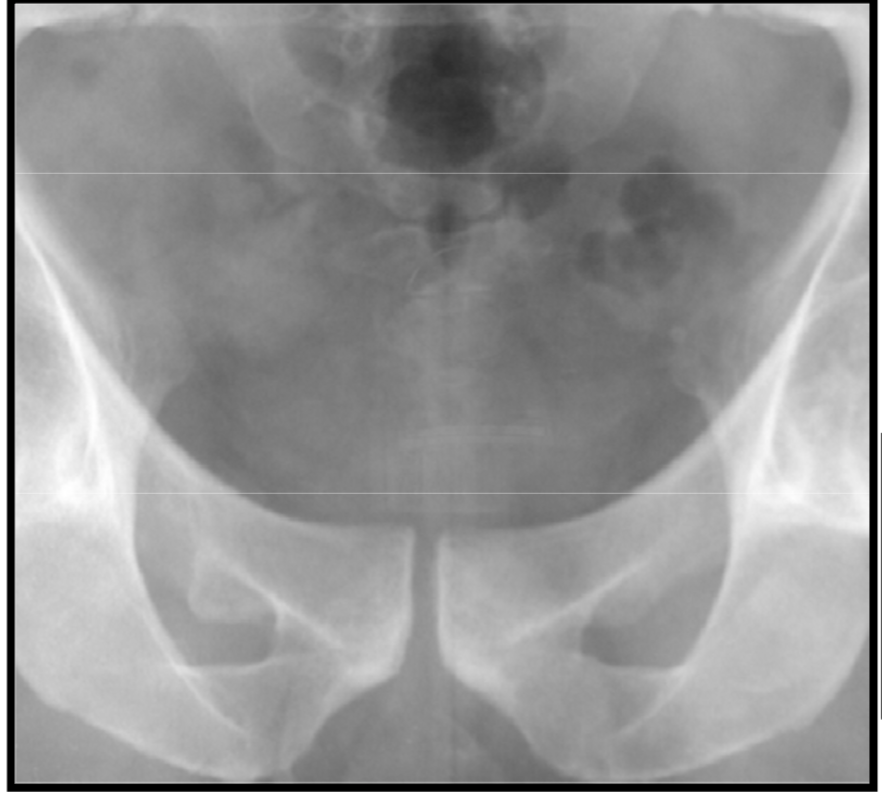

Paraglenoid sulcus – internal iliac artery

anat variation

Degenerative enthesopathy

Pubic ears – another degenerative enthesopathy

Phlebolith’s (calcified venous thrombi)

Bone islands

variation anat

à comparer voir si ce n’est pas une métastase ostéoblastique